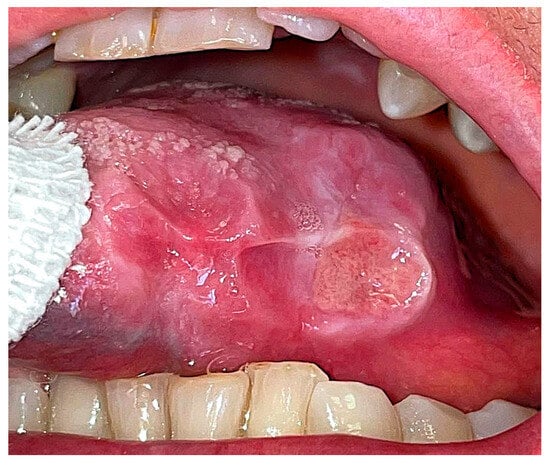

A 69-year-old Caucasian female was referred to the Department of Oral and Maxillo-Facial Sciences for the clinical evaluation of a wide ulcer on the left posterior margin of the tongue (Figure 1).

Figure 1. (A) Intraoral pre-operative aspect of the ulcer on the left margin of the tongue. The ulcer shows a yellowish central area and indurated margins. The togue margin exposes the indentation of the teeth occlusion. (B). The dotted line indicates the area of biopsy.

The intraoral examination revealed a wide ulcer (2 cm × 3 cm) on the left posterior margin of the tongue. The ulcer borders appeared erythematous, elevated and indurated while the central bed showed flat yellowish fibrin. There were no palpable lymph nodes. Due to her multiple chronic health conditions, the patient demonstrated signs of frailty, a condition marked by heightened vulnerability to stressors resulting from diminished physiological reserves.